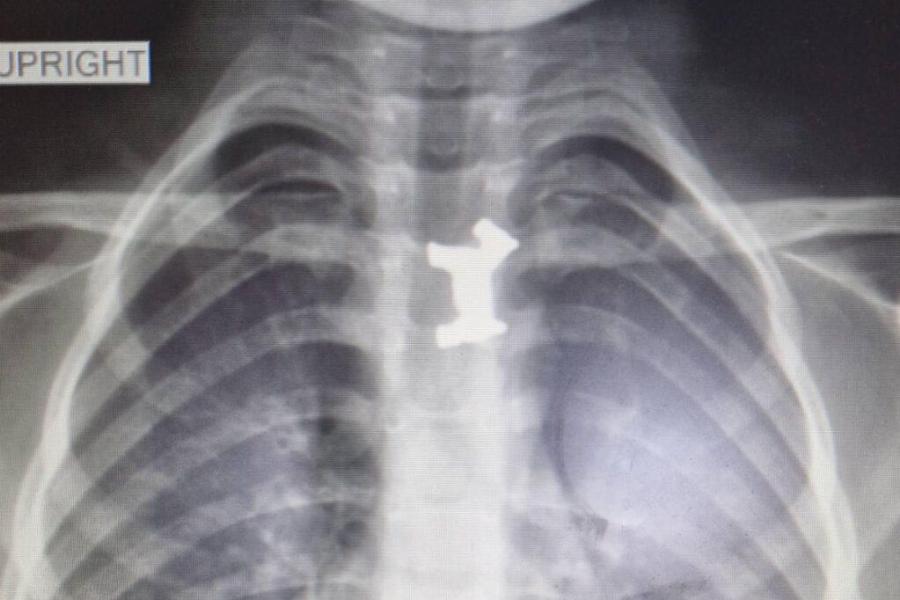

Ένα αγόρι ηλικία 5 ετών κέρδισε τη μάχη για τη ζωή, καθώς κατάπιε ένα μεταλλικό παιχνίδι και οι γιατροί κατάφεραν να του σώσουν τη ζωή. Η χειρουργική επέμβαση του αγοριού από τις Σέρρες πραγματοποιήθηκε το πρωί της Τρίτης. Οι παιδογαστρεντερολόγοι μαζί με τους παιδοαναισθησιολόγους του Ιπποκρατείου Νοσοκομείου, κατάφεραν να αφαιρέσουν επιτυχώς το μεταλλικό σκυλάκι από τον οισοφάγο του.

Το αγοράκι εμφάνισε σιελόρροια και οι γονείς του το πήγαν στο Γενικό Νοσοκομείο Σερρών. Εκεί, εξετάστηκε από τους γιατρούς και η ακτινογραφία έδειξε ότι είχε καταπιεί και είχε σφηνώσει στον οισοφάγο του ένα μεταλλικό παιχνίδι. Αποφασίστηκε η διακομιδή του στο Ιπποκράτειο Νοσοκομείο Θεσσαλονίκης.

Εκεί οι παιδίατροι ακολούθησαν την προβλεπόμενη διαδικασία σε αντίστοιχες περιπτώσεις. Το πρωί υποβλήθηκε σε χειρουργική επέμβαση και οι γιατροί κατάφεραν να αφαιρέσουν με επιτυχία το μεταλλικό σκυλάκι από τον οισοφάγο του παιδιού.